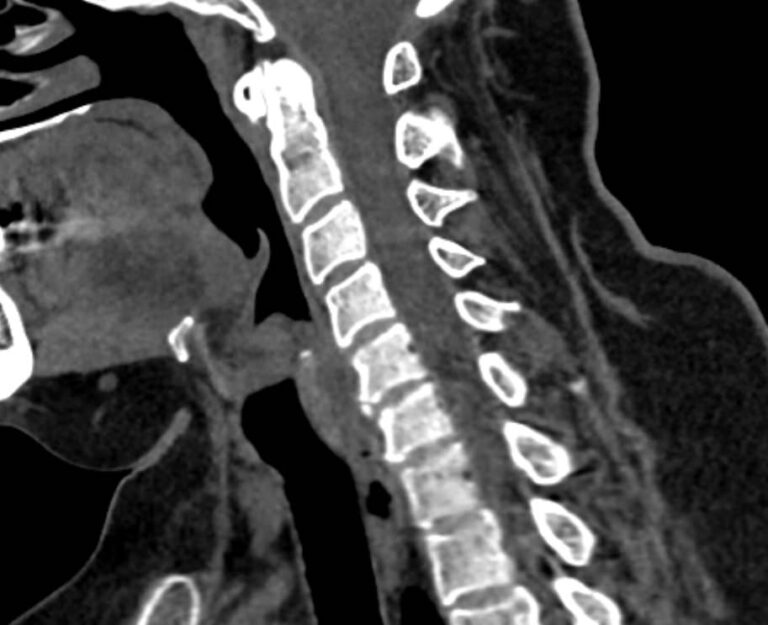

Мультиспиральная компьютерная томография является одним из наиболее информативных методов диагностики дегенеративно-дистрофических заболеваний, травматических, воспалительных изменений, а также опухолевых процессов позвоночника. Методика предусматривает использование рентгеновского излучения для получения детализированных снимков костных структур позвоночника, межпозвонковых суставов и межпозвоночных дисков.

При подозрении на распространенный процесс с поражением различных уровней позвоночного столба показано проведение мультиспиральной КТ трех отделов позвоночника.

В клинике «Доступная медицина» установлены современные мультиспиральные компьютерные томографы экспертного класса TOSHIBA AQUILION в различных модификациях (64-срезовый и 128-срезовый), на которых выполняются комплексные обследования позвоночника, включая одномоментное исследование несколько отделов. Аппараты производят сканирование с помощью рентгеновских лучей, делая тончайшие срезы с шагом от 0,5 мм, затем с помощью компьютерных программ полученные данные преобразуются в изображения трехмерного формата, что обеспечивает точность и достоверность диагностики.

С помощью мультиспиральной КТ можно диагностировать:

- дегенеративно-дистрофические заболевания позвоночника (остеоартроз, спондилез, деформирующий спондилоартроз);

- травматические повреждения позвоночника (компрессионные и оскольчатые переломы);

- стеноз (сужение) позвоночного канала;

- грыжи межпозвонковых дисков (протрузии, экструзии и грыжи Шморля);

- спондилиты, гнойные артриты, сакроилеит, абсцессы околопозвоночных тканей и другие воспалительные заболевания, туберкулез;

- хронические системные заболевания позвоночника (болезнь Бехтерева);

- опухоли позвоночника и окружающих тканей;

- патологические изгибы позвоночника, сколиоз, усиленный или выпрямленный лордоз как нарушение статической функции позвоночника;

- аномалии строения позвоночника.